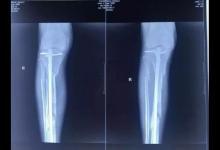

2017年10月18日下午,張毅在廊坊師范學院院內(nèi)被三名男子打傷。從監(jiān)控視頻看,下午5時17分,三名身穿黑衣戴黑帽的男子突然躥出,其中一人將張毅撲倒,另外兩人持鎬毆打張毅。隨后,三人坐著白色無牌越野車離開,全程只持續(xù)了十幾秒。

經(jīng)過診斷,張毅右小腿粉碎性骨折,左腿軟組織挫傷。

李勇說,院長做過那么多骨科手術(shù),肯定從一開始心里就清楚,這種粉碎性骨折很難治好。他手術(shù)后沒過幾天,就回到醫(yī)院休養(yǎng)。“嘴上說沒事兒,但他給病人講了一輩子怎么練習拄拐,怎么恢復鍛煉,現(xiàn)在反而自己要面對這些。”

尤力表示,直到出事前,張毅的腿傷還沒有養(yǎng)好,平時只能靠拄雙拐走路。